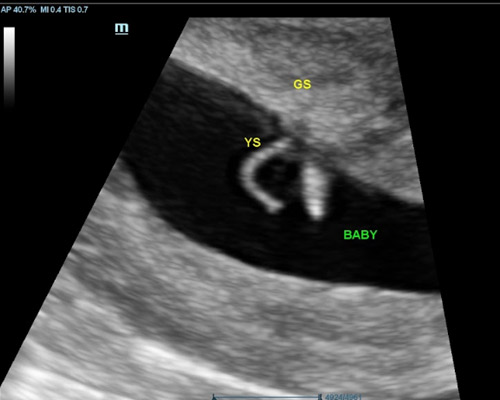

A reassurance scan is an ultrasound carried out during pregnancy to check on your baby’s wellbeing between routine appointments. Many parents choose this scan when they want extra peace of mind or simply wish to see their baby again.

During the appointment, the sonographer looks at key aspects such as the heartbeat, movements, activity levels, and position. This type of scan helps confirm that everything is progressing as expected.

Ultrasound scanning is a safe and non-invasive method that uses sound waves to create images. It does not involve radiation and has been widely used for many years.

You will be able to see your baby’s movements, heartbeat, and position on the screen during the appointment.